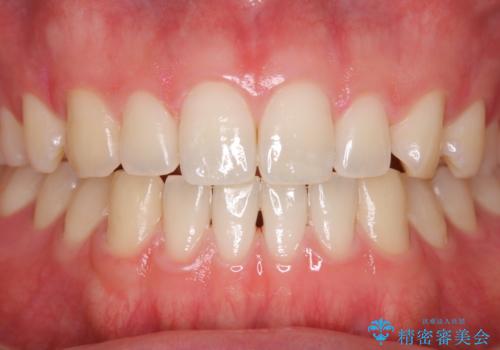

- 虫歯予防のため、クリーニングと歯磨き指導を希望とのことでした。PMTC30分コース、歯磨き指導を行いました。

- 5千円+tax費用は治療当時の料金となります